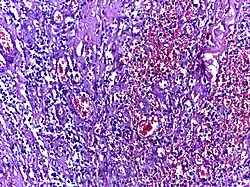

![]() |

Neutrophils | Micrograph showing neutrophils in acute inflammation. | Category: Neutrophils | Neutrophil |